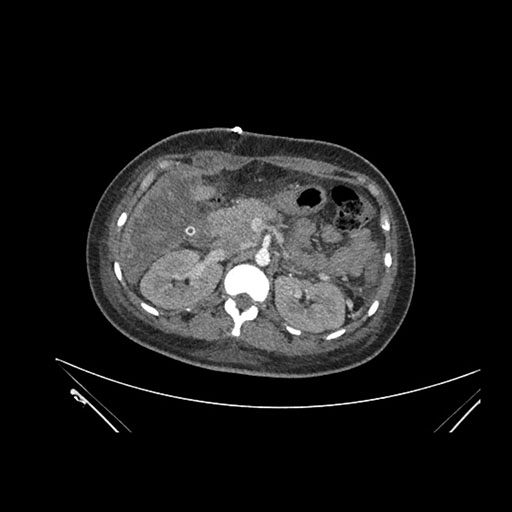

Imaging Analysis

Look through the patient's CT scan to identify any areas of concern for the necessary procedure.

Based on initial findings, which issue(s) would you be most concerned about?